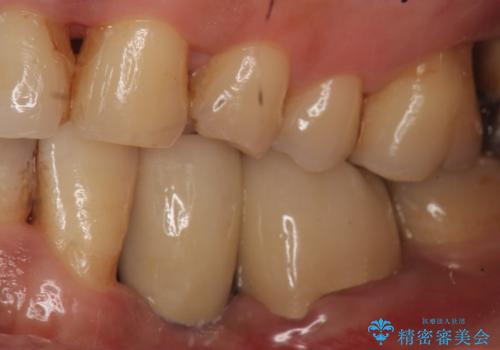

左下6も再根管治療後、オールセラミッククラウンによる補綴を行いました。

オールセラミッククラウンについて

今回用いたオールセラミッククラウンはジルコニアフレームという白い素材の上にセラミックを盛っているため、審美性が非常に高いのが特徴です。

また、ジルコニアは人工ダイヤモンドの材料にも使われているほど高い強度を持っており、そのためオールセラミッククラウンは審美性だけでなく、奥歯やブリッジの補綴も可能とするクラウンです。